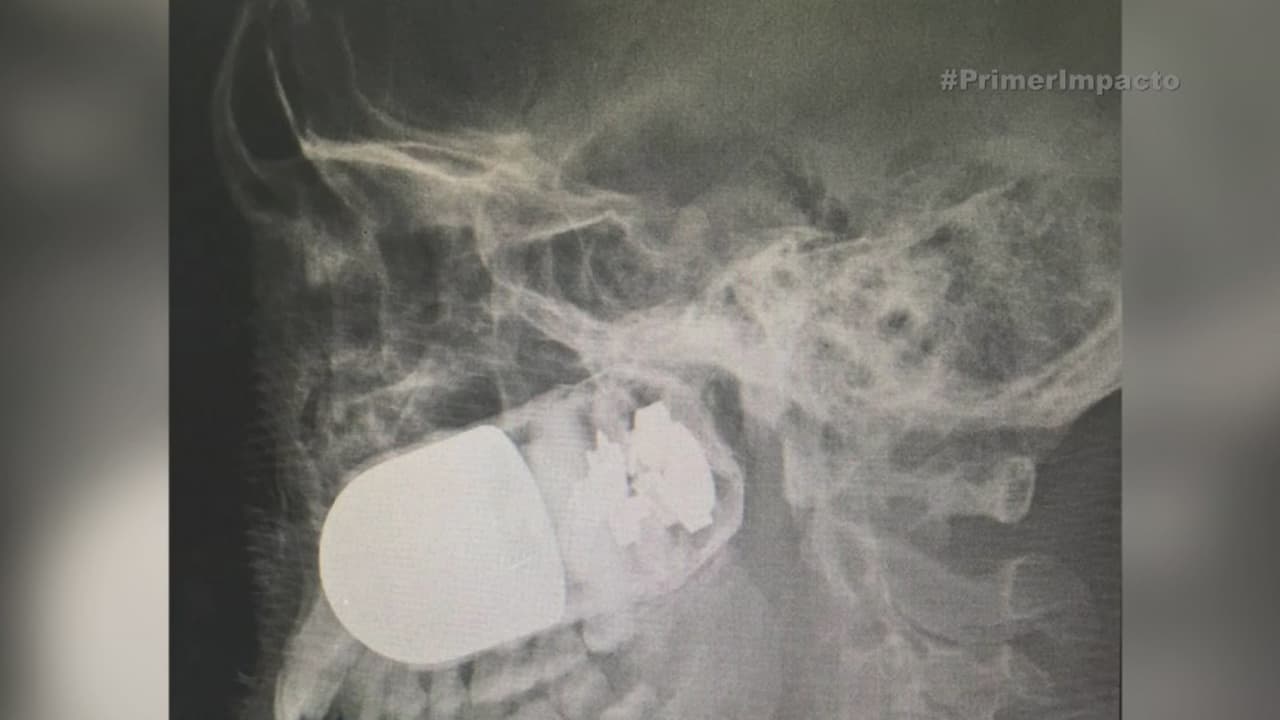

Soldado terminó con una granada clavada en el rostro

El uniformado terminó con el explosivo incrustado en la cara cuando su compañero activó un lanzagranadas por error, en Colombia.